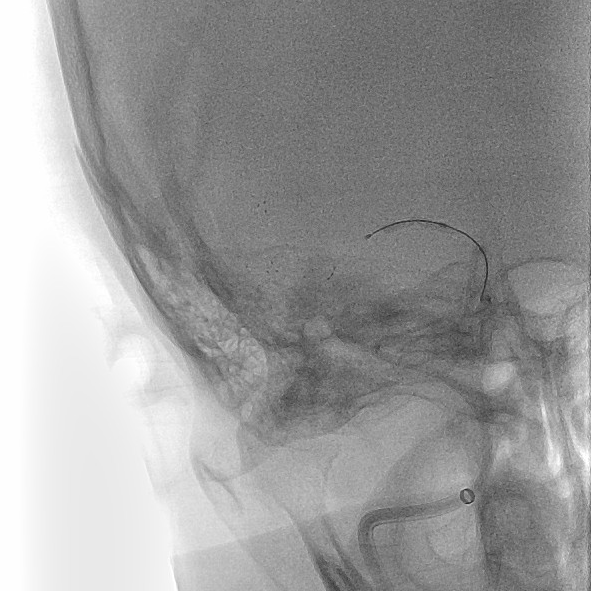

造影评估:

2.0×15mm球囊加压时可见“腰”,加压至8ATM维持5min。

扩张后造影见血流改善,支架内未见明显血栓影。

观察10分钟回收支架后,继续观察15分钟提示血流良好。

从完成穿刺到血管开通总用时仅40分钟。